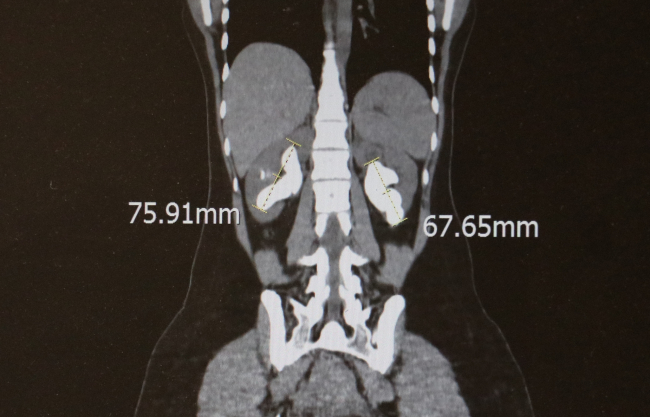

Diyarbakır'da şiddetli böbrek ağrısı çeken bir kişi, Dicle Üniversitesi Tıp Fakültesi Hastanesi'ne başvurdu. Sol böbreğinde 6,5, sağ böbreğinde ise 7 santimetrelik taşlar tespit edildi. 100'den fazla parçaya bölünen tek böbrekteki taş, 10 saatlik kapalı ameliyatla çıkarıldı.

Şiddetli ağrı şikayetiyle hastaneye başvurdu. Kontroller sonrası böbreğinde 6 buçuk ve 7 santimetrelik taşlar bulundu.

Operasyonda 6,5 santimetrelik taş 100 parçaya ayrıldı.